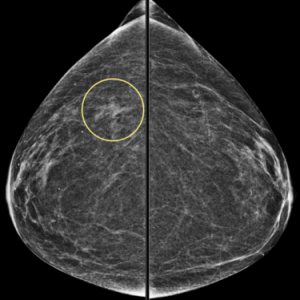

Explanation: A mass with this type of popcorn-like calcifications is almost certainly a fibroadenoma and benign. Having prior mammograms which demonstrate little or no change over time can increase your confidence.

In this patient’s case, there is gradual involution (and slowly increasing calcifications) of this fibroadenoma (image on the left) compared to mammogram five years prior (image on the right):